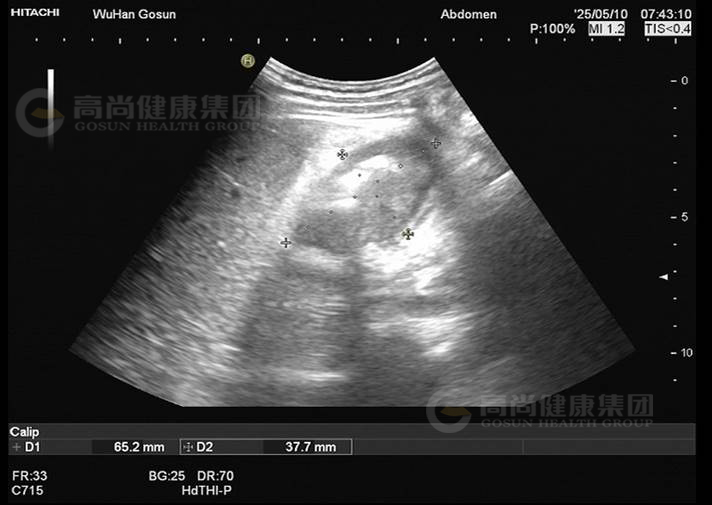

· 超声图像

图1-正常右肾

图2-肝肾间隙包块

图3-肝肾间隙包块

图4-肝肾间隙包块

超声表现及意见:

肝肾间隙可见不均质包块,大小约7.5×6.5×5.2cm,界欠清,轮廓欠规整,壁厚,部分切面周边见高回声晕,内回声不均匀,呈假肾征,包块内部及周边血流信号不明显。

超声提示:

肝肾间隙不均质包块,考虑结肠或腹膜来源,建议进一步检查。